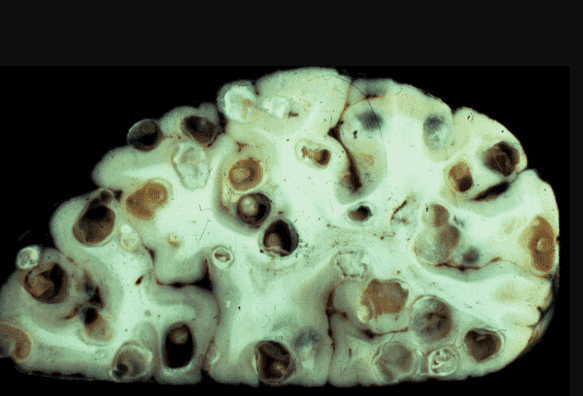

На фото нижче можете побачити знімок кишечника. Пацієнтка померла від раку кишківника, спричиненого паразитами. Паразити отруюють здорові клітини своїми токсинами, через що вони змушені перероджуватися, змінювати свою структуру. І перероджуються вони саме в ракові клітини, які агресивніші й здатні протистояти паразитам. Але для людини ці клітини згубні. Пухлина швидко розвивається і метастазує. Людина гине протягом лічених місяців.

"Ходи" паразитів у просвіті кишечника

Мозок, уражений паразитами